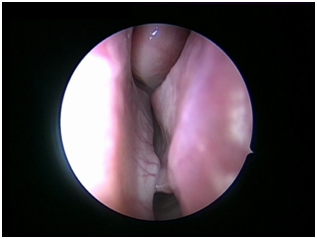

Nasal Endoscopy is done to assess the septal deviation and spurs (Figure 1) ( Figure 2). Septal infiltration is carried out with a solution of 2% Xylocaine with 1: 100,000 adrenaline in the sub-mucosal plane. It is given with a single prick at the inferior most part of the nasal septum at the junction of the septum with the floor of the nasal cavity anterior to the mucocutaneous junction. The infiltration is given at the same point on both the sides (Figure 3). The incision is always given on the deviated side. It is given anterior to the mucocutaneous junction because the skin present at that place is thick and chance of a tear of the flap is less (Figure 4). The mucoperichondrial flap is raised on the deviated side with a Freer’s elevator strictly under vision. The flap is not to be raised beyond the deviated part because the part of the septum posterior to the deviation is not under direct vision (Figure 5) (Figure 6). The caudal end of the septum is then palpated and an incision is given on the cartilage 1cm behind the columella. This 1cm of the cartilage is saved to prevent post operative tip deformities (Figure 7). The cartilage is sliced and the opposite side is entered, the mucoperichondrial flap of the opposite side is then elevated with a Freer’s elevator. A cut is given in the septal cartilage as high as possible. A septal window is created and a Ballenger’s swivel knife is taken and lodged in the place where the cartilage was cut. Creation of a septal window thus increases the area of exposure (Figure 8) (Figure 9). The flap on the non-deviated side is elevated till the bony-cartilaginous junction.

Figure 3 Infitration.

Figure 4 Skin incision.